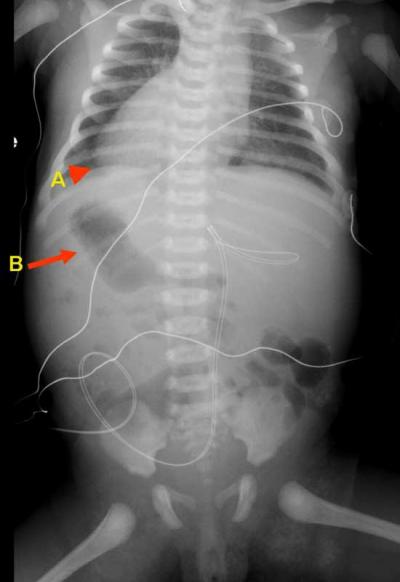

হার্ট যাদের বুকের ডান পাশে ( Dextrocardia )

একটু অবাক লাগলেও ব্যাপারটা সত্যি। আমাদের চারপাশেই এমন অনেক মানুষ আছে যাদের বুকের ডান পাশে হার্ট বা হৃদপিন্ড আছে। অথচ তারা হয়ত জানেন না।

যাদের বুকের ডানপাশে হার্ট আছে তাদের সংখ্যা প্রতি ১২ হাজারে মাত্র ১ জন। হার্টের এই অসাধারণ অবস্থান করাকে বলে Dextrocardia। অনেকে ডাক্তার Dextrocardia রুগিদের ধরতে পারে না। আমি নিজের চিকিৎসা করিয়েছিলাম দীর্ঘ ৩ বছর। তবে সেটা রিমুটিক ফিভারের জন্যে। আমার ডাক্তার কখনই ধরতে পারেনি যে আমার হার্ট ডান পাশে।

মজার ব্যাপার হল, আমার পাকস্থলিটাও উল্টো পাশে মানে ডান পাশে। ভয় পাবার কিছু নেই। অন্তত আমার কোন সমস্যা নেই। Dextrocardia নিয়ে আরও জানতে লিঙ্ক